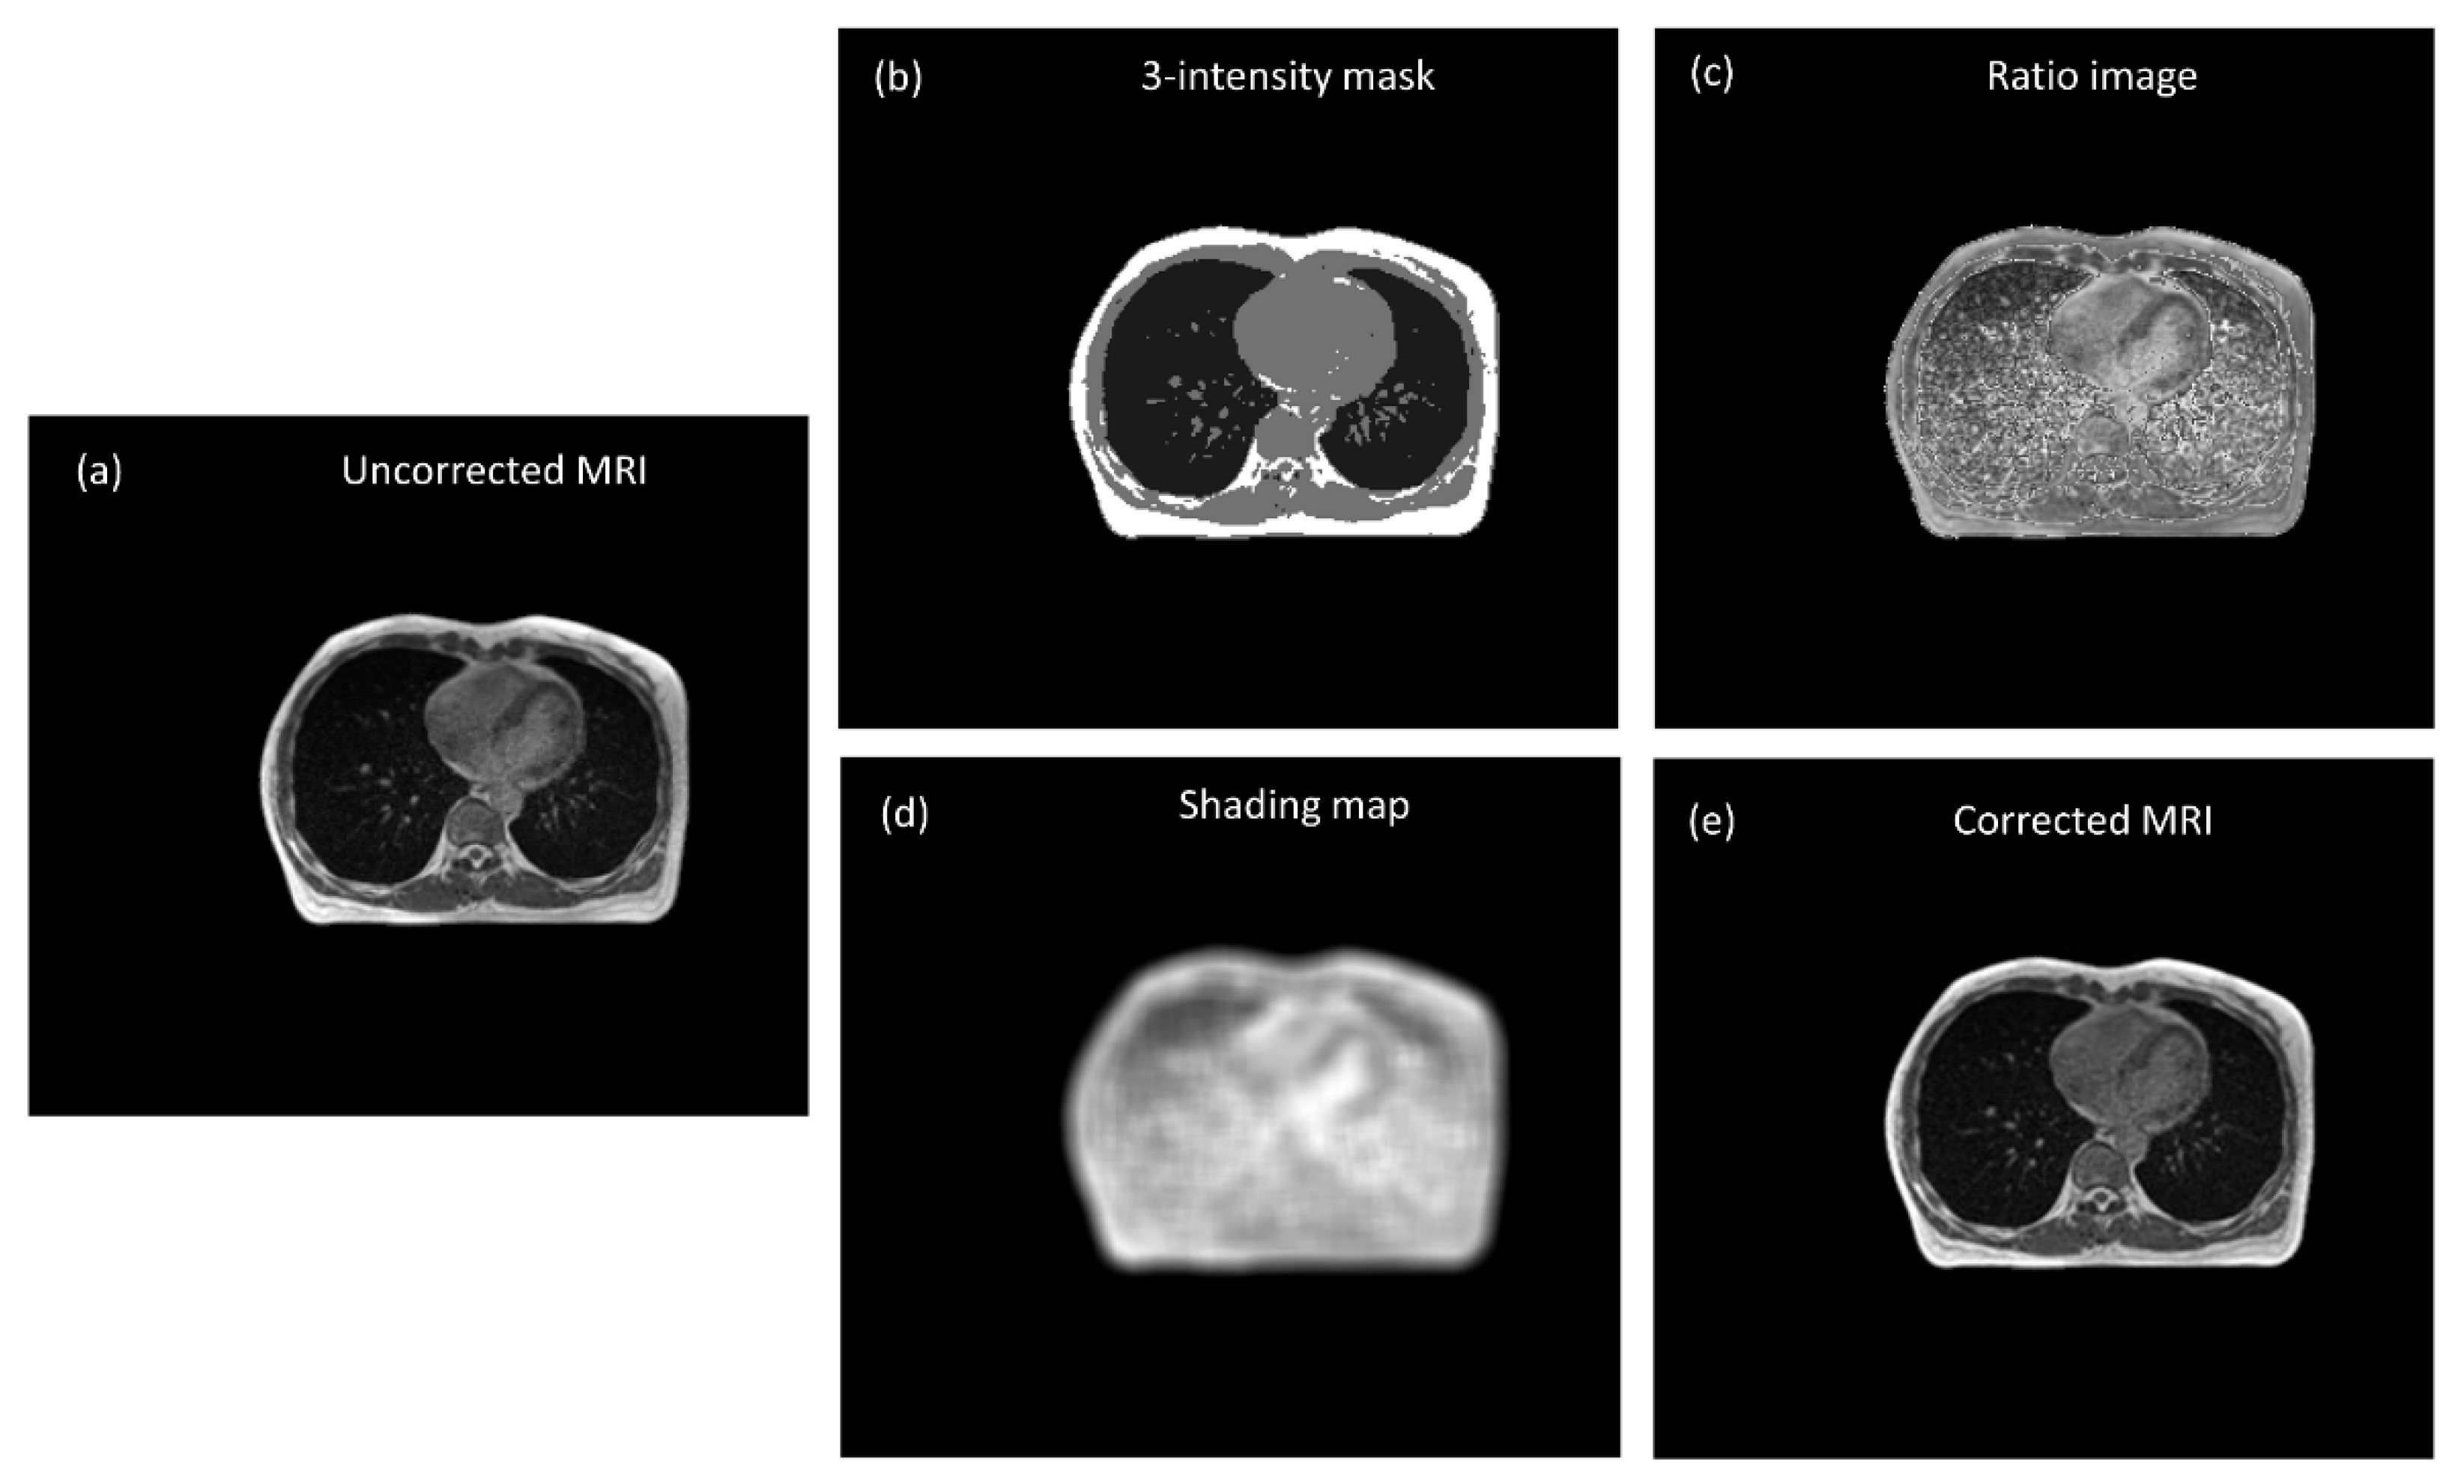

3.1. Chest Imaging for Cancer Treatment